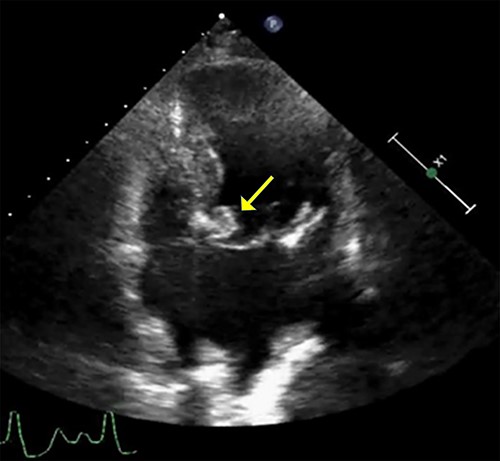

An 86-year-old woman with a history of hypertension and hyperlipidemia presented to our hospital with episodes of syncope lasting several minutes. On admission, her consciousness was clear, and there were no significant neurological findings on physical examination. Electrocardiography showed sinus rhythm at 79 bpm. Laboratory findings showed no abnormalities in electrolytes or anemia that could cause syncope. The coronary angiogram showed 90% stenosis of the right coronary artery (RCA). Transthoracic echocardiography (TTE) and transesophageal echocardiography (TEE) both showed a mobile mass with a maximum diameter of 12 mm on the anterior annulus of the mitral valve (Figs 1 and 2). TTE showed normal left ventricle (LV) function with an ejection fraction of 60%, LV wall motion was within the normal range and no significant valvular disease was detected. Preoperative chest computed tomography showed severe mitral annular calcification (MAC) (Fig. 3).

Transthoracic echocardiogram. A well-defined densely calcified mass noted on the anterior mitral leaflet in the apical four-chamber view.